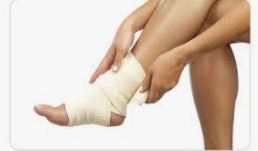

| 복숭아뼈 부음 치료방법

물혹의 경우에는 주사기로 물을 빼주는데 이러한 방법은 근본적인 치료 방법이 아니기 때문에 재발이 잘되고 자주 물을 빼내줘야하는 번거로움이 있습니다. 점액낭염이라면 소염제등 염증을 없애주는 약을 처방받아 복용하기도 합니다. 관절 누공이라면 뼈에 문제가 생긴 것이기 때문에 정형외과에서 진단을 받으시고 치료를 받는것이 좋습니다.